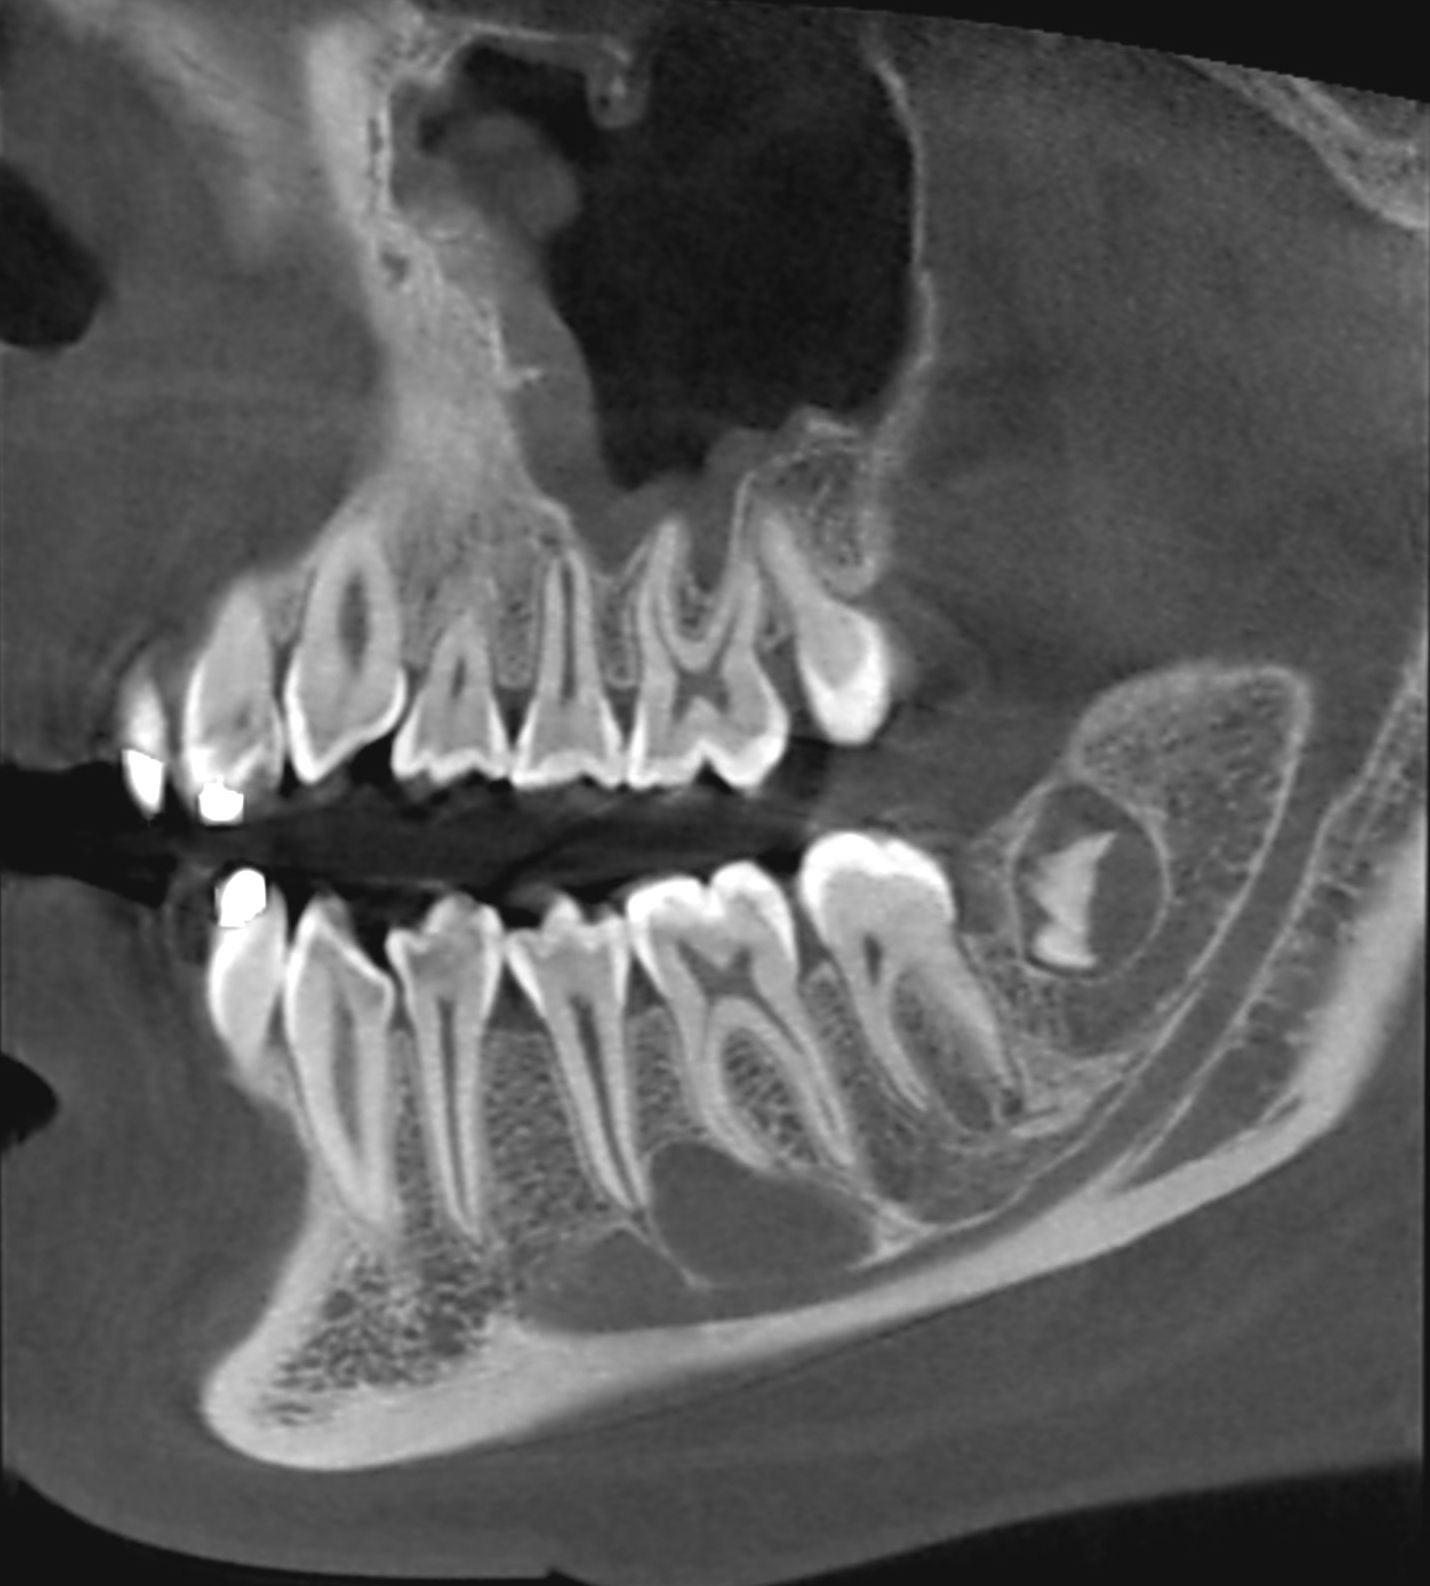

Le cone beam est une nouvelle technique de radiographie numérisée situé entre le panoramique dentaire et le scanner, il utilise un faisceau d’irradiation de forme conique d'où son nom. Cet appareil présente notamment l’avantage d’être plus précis que le panoramique dentaire et il possède une résolution similaire, voire supérieure à celle du scanner, avec en plus la possibilité d’une reconstruction numérique en 3D.

Le cone beam utilisé en pathologie dentaire et maxillo-faciale est indiqué pour l’examen des tissus minéralisés (dents, cartilages, os), il permet d’identifier les lésions osseuses, les fractures, les infections, les kystes ou les corps étrangers.

Le cone beam dentaire est par exemple indiqué dans les pathologies suivantes :

- pathologies infectieuses

- pathologies du parodonte

- pathologies osseuses des maxillaires

- kystes radiculaires

- dents incluses, surnuméraires

- implants dentaires

Les nouvelles générations de scanner permettent de faire une acquisition d’un volume global d’une partie du corps et de travailler à l’intérieur de ce volume en isolant une structure anatomique donnée et de l’explorer dans tous les plans de l’espace.

Grace à la technique de seuillage il est possible de dissocier progressivement les dents des structures osseuses environnantes dans le volume donné.